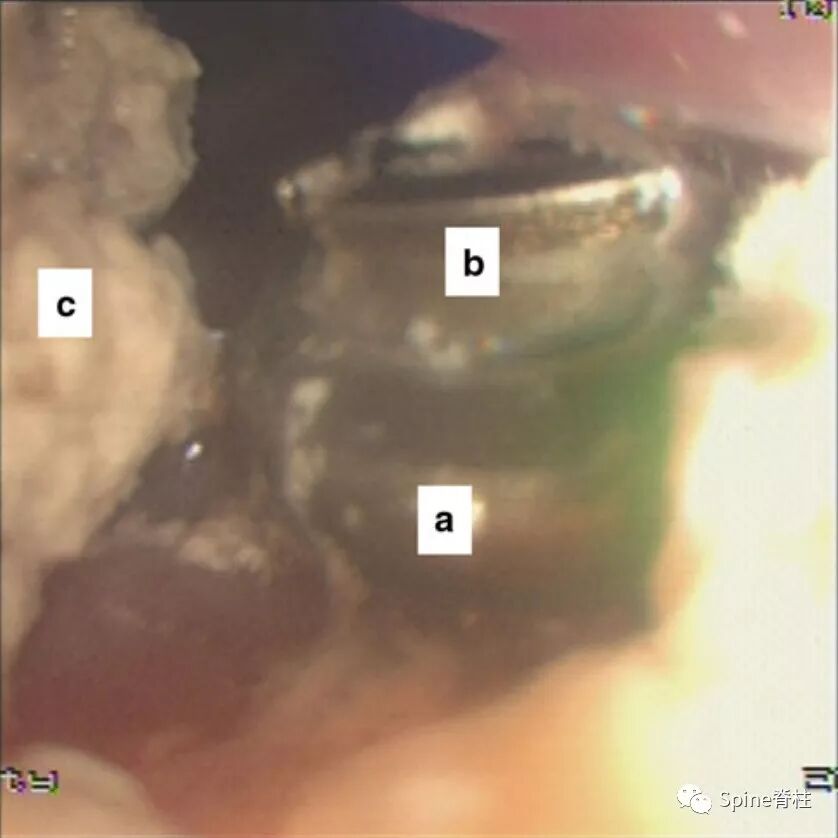

图示:内窥镜照片。经过仔细检查,我们食管憩室的一角发现了钢板的边缘“a”和螺丝“b”。“c”表示前一天吞钡后的剩余钡。

肌肉皮瓣加固修复完成。a:胸骨舌骨肌瓣,b:舌骨肌瓣,c:引流管。